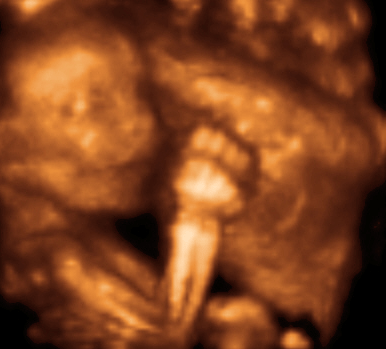

High point: Our 3D ultrasound, where we found out we’re having a baby boy! It is so nice to know the sex, and actually get to buy cute gender-specific clothes — not to mention it’s a huge relief to be able to start the nursery. If any of you are contemplating finding out the sex, I highly recommend it.

p.s. your little boy is soo cute!